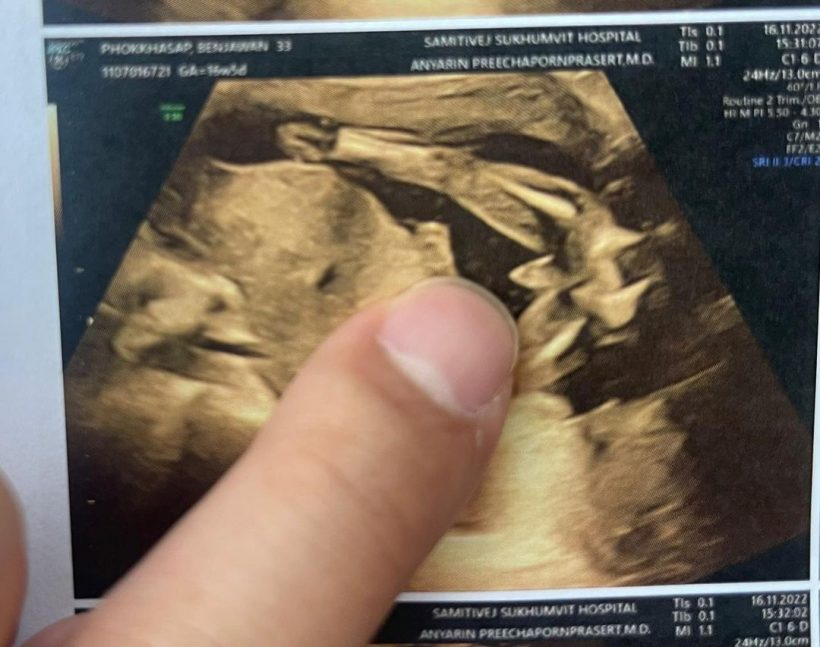

ล่าสุด หนูเล็ก เผยภาพอัลตราซาวนด์ลูกน้อยในครรภ์ พร้อมเฉลยเพศลูก ว่า “เพศลูก ผู้ชายนะคร้า ผงาด โชว์แต่เด็กเล้ยยยยย “

Cr_ig: nuulekk_benjawan